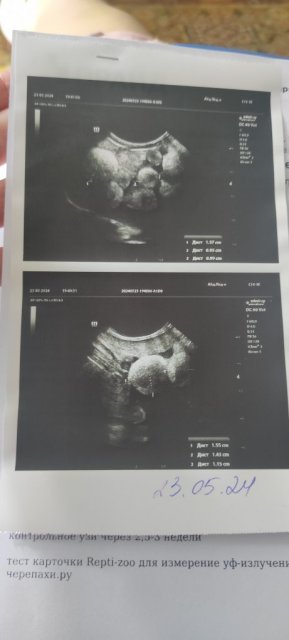

@moth сходили, перитонита нет слава богу, но яйца неправильно формируются. Записались на завтра на удаление яичников. Ходили к Новокрещеновой Н.А. В прайд на Ленинском 98. Удалять будет она же.

IMG_2024_06_11_20_05_49_0422304919056462195014.jpg

IMG_2024_06_11_20_06_46_2992232832442358652938.jpg